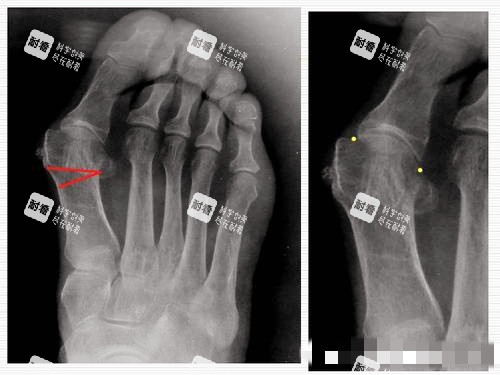

1. 采用三维立体矫正方案,通过术前详细影像评估,定制个性化手术路径,确保操作针对性强。

1. 术前多方面评估:包括足部检查、影像学分析和健康状况筛查,以制定靠谱方案。